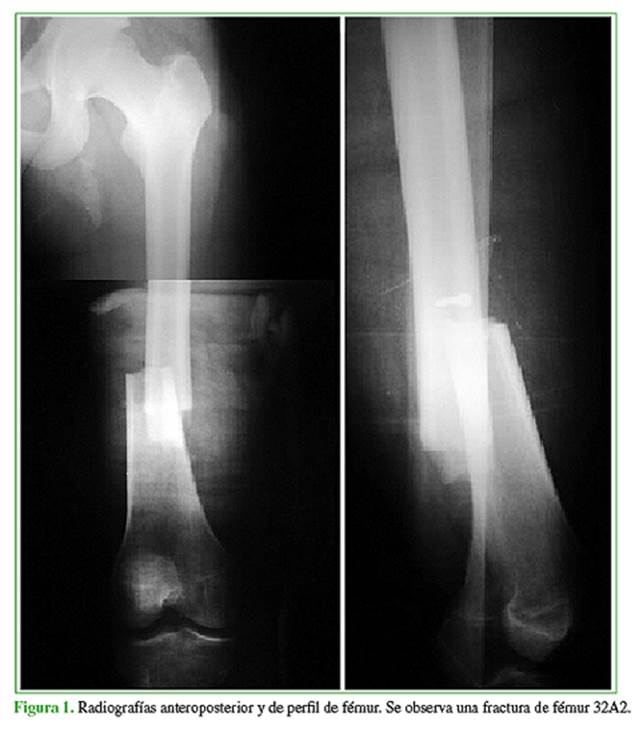

Varón de 17 años de edad que ingresó por un politraumatismo a causa de un accidente de moto contra un automóvil, en el que sufrió una fractura transindesmal de tobillo izquierdo y una fractura de fémur derecho, tipo 32A2 de la clasificación AO, asociadas a un trauma de tórax (Figura 1).

Inicialmente la fractura de fémur se estabilizó con un tutor externo y la fractura de tobillo, con una valva de yeso. Al octavo día se realizó la conversión del tutor externo a clavo endomedular retrógrado de fémur de 9 mm x 350 mm no fresado (Figura 2).